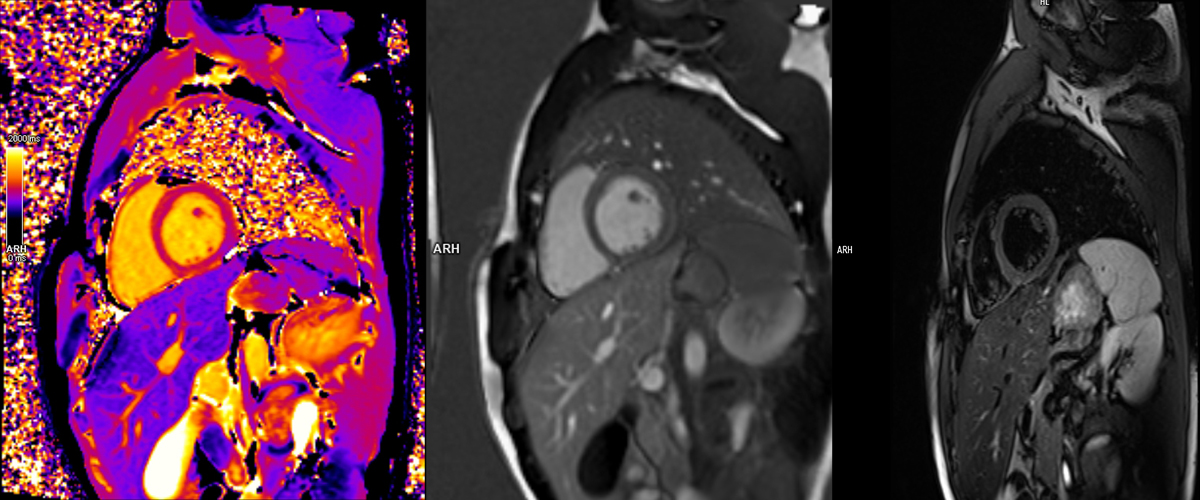

Kardiyak MR , kalp ve çevresindeki yapıların ayrıntılı ve net görüntülerini elde etmek için manyetik alan ve radyo dalgaları kullanan non-invaziv bir görüntüleme yöntemidir. Bu yöntem, kalp hastalıklarının teşhis ve takibinde oldukça hassas ve güvenilir bir yöntemdir. Radyasyon içermemesi ve detaylı bilgi sağlaması nedeniyle birçok durumda tercih edilir.

• Dinamik görüntüler sağlar: Kalbin hareketlerini, kasılma gücünü ve kan akışını gerçek zamanlı olarak gösterir.

• Hassasiyet: Kalp dokusu, damarlar ve çevre yapılar hakkında yüksek çözünürlüklü görüntüler sunar.

• Dinamik Görüntüleme: Kalbin hareketlerini gerçek zamanlı olarak görüntüler.